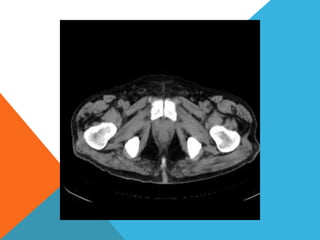

El paciente presentó síntomas de sangrado digestivo y pérdida de peso. Exámenes revelaron gastritis crónica asociada a H. pylori. Un tumor fue descubierto en una colonoscopia normal. La cirugía removió un tumor fibroide solitario, una rara neoplasia mesenquimal que usualmente crece lento y tiene bajo potencial de malignidad. El pronóstico después de la remoción quirúrgica es generalmente bueno.